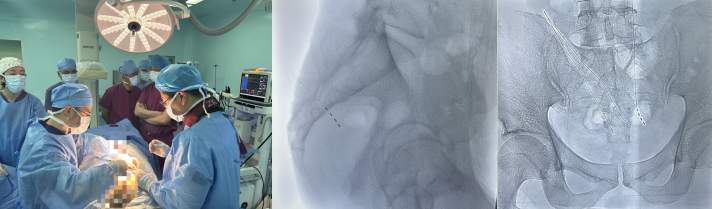

2024年2月22日,为患者实施骶神经调控一期电极植入术,手术顺利,按预期完成。术中电极植入精准,4个触点分别在0.7mA、0.6mA、0.3mA及0.6mA引出运动反射。术后顺利转入一期测试体验治疗。一期手术由方克伟教授、杨童欣副教授等共同完成,历时约60分钟。

经过2周的一期测试体验治疗,患者尿频、尿急、夜尿、便秘、排尿困难及夜尿引起的睡眠问题等症状均获得明显改善,患者对骶神经调控效果满意,于2024年3月6日,进行了InterStim骶神经调控二期刺激器植入术(即永久植入)。